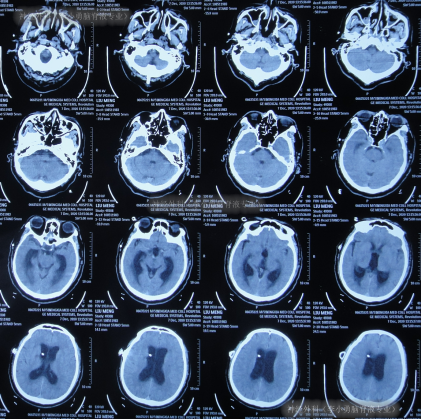

住院1周左右时间,期间曾3次查头颅CT(图-2)示脑室稍有扩张,但头晕症状慢慢消失,行走不稳缓解,认为“病情变好”出院。

图-2:3次查头颅CT